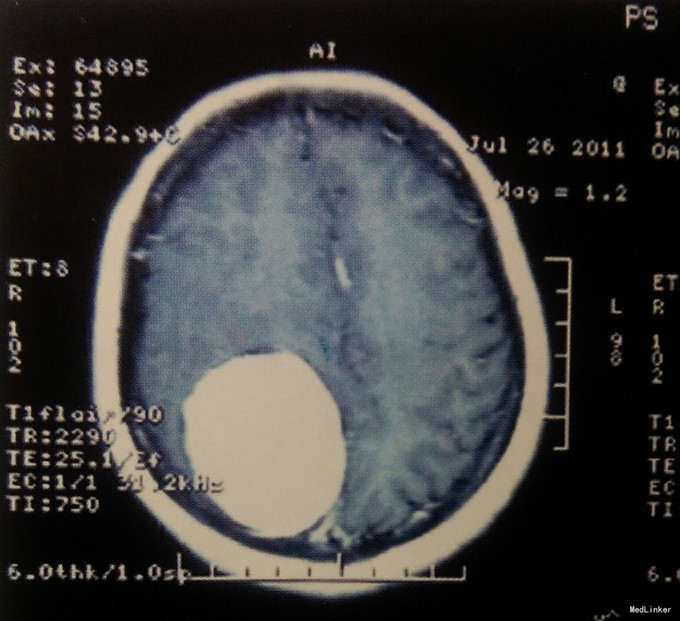

患者,女,48岁。主因“头痛、头晕2年加重伴左侧肢体无力半年”入院。 患者于2年前无明显诱因出现头痛,以双颞部为著,呈持续性胀痛,无恶心、呕吐,不伴四肢抽搐,未行特殊治疗。近半年来自觉头痛、头晕加重,伴左侧肢体无力,至当地医院就诊,行头颅MRI示右顶脑肿瘤。为求进一步治疗特来我院,门诊以“右顶窦旁镰旁巨大脑膜瘤”收入我科。无恶心、呕吐等其他症状,无癫痫病史及精神异常,既往无特殊病史。

入院查体:左侧肢体肌力Ⅳ级,右侧肢体肌力Ⅴ级,肌张力正常;余神经系统查体未见明显异常体征。 术前影像学检查 入院后在我院行颅脑CT增强、MRI增强片示:右顶窦旁镰旁巨大占位性病变,多考虑脑膜瘤。

入院诊断:右顶窦旁镰旁巨大脑膜瘤。 治疗:患者入院后完善各项术前检查,在全麻下行开颅探查右顶窦旁镰旁巨大脑膜瘤切除术。